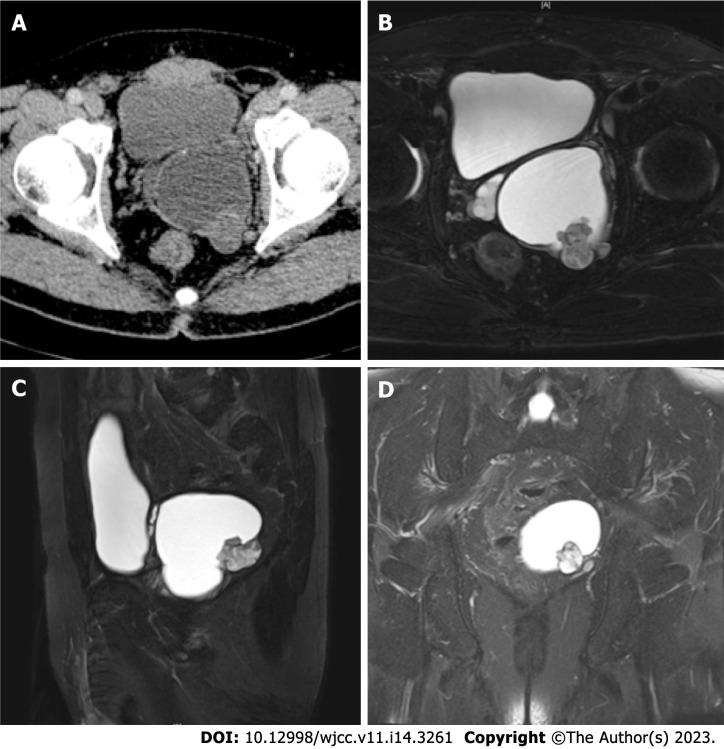

A 54-year-old man with an 18-year history of a seminal vesicle cyst presented with worsening hematospermia that had persisted for one month. Dynamic contrast-enhanced computed tomography and pelvic magnetic resonance imaging indicated a mass with a cystic-solid component. Robot-assisted seminal vesicle tumor resection was performed, and primary seminal vesicle adenocarcinoma was confirmed pathologically. The patient received pelvic radiotherapy for six weeks, and to date, no evidence of recurrence has been found.

一名有18年精囊囊肿病史的54岁男性,出现持续1个月的血精加重症状。动态对比增强计算机断层扫描和盆腔磁共振成像显示有一个囊实性成分的肿块。实施了机器人辅助精囊肿瘤切除术,病理证实为原发性精囊腺癌。患者接受了为期六周的盆腔放疗,迄今为止,未发现复发迹象。